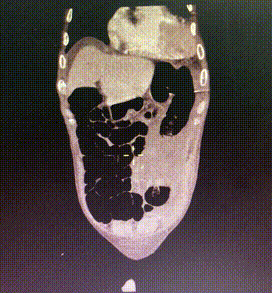

术后行急诊CT检查

TAVR术后3日Hb较前下降 (63g/L)

CT提示左侧腹膜后、髂窝及腹股沟区巨大血肿